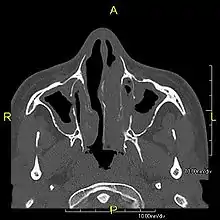

Around 80% of people with primary ciliary dyskinesia experience respiratory problems beginning within a day of birth. Many have a collapsed lobe of the lung and blood oxygen low enough to require treatment with supplemental oxygen.[1] Within the first few months of life, most develop a chronic mucus-producing cough and runny nose.[1] The main consequence of impaired ciliary function is reduced or absent mucus clearance from the lungs, and susceptibility to chronic recurrent respiratory infections, including sinusitis, bronchitis, pneumonia, and otitis media. Progressive damage to the respiratory system is common, including progressive bronchiectasis beginning in early childhood, and sinus disease (sometimes becoming severe in adults). However, diagnosis is often missed early in life despite the characteristic signs and symptoms.[2] In males, immotility of sperm can lead to infertility, although conception remains possible through the use of in vitro fertilization, there also are reported cases where sperm were able to move.[8] Trials have also shown that there is a marked reduction in fertility in females with Kartagener's syndrome due to dysfunction of the oviductal cilia.[9]

Many affected individuals experience hearing loss and show symptoms of otitis media which demonstrates variable responsiveness to the insertion of myringotomy tubes or grommets. Some patients have a poor sense of smell, which is believed to accompany high mucus production in the sinuses (although others report normal – or even acute – sensitivity to smell and taste). Clinical progression of the disease is variable, with lung transplantation required in severe cases. Susceptibility to infections can be drastically reduced by an early diagnosis. Treatment with various chest physiotherapy techniques has been observed to reduce the incidence of lung infection and to slow the progression of bronchiectasis dramatically. Aggressive treatment of sinus disease beginning at an early age is believed to slow long-term sinus damage (although this has not yet been adequately documented). Aggressive measures to enhance clearance of mucus, prevent respiratory infections, and treat bacterial superinfections have been observed to slow lung-disease progression. The predicted incidence is 1 in approximately 7500.[10]

When accompanied by the combination of situs inversus (reversal of the internal organs), chronic sinusitis, and bronchiectasis, it is known as Kartagener syndrome[3] (only 50% of primary ciliary dyskinesia cases include situs inversus).[11]